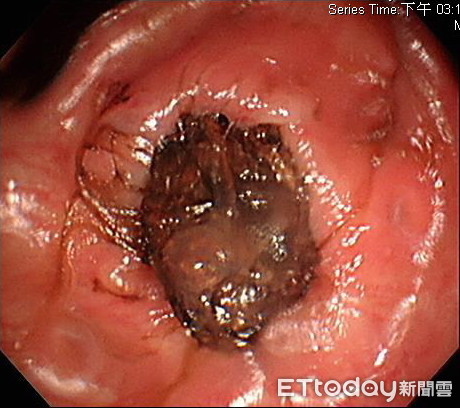

錢政弘表示,透過大腸鏡檢查,婦人在大小腸的交界處,卡了許多乒乓球大的糞石,硬到根本無法敲開破壞,透過喝橄欖油潤滑腸道,搭配軟便藥的服用,一天以後,患者才陸續排出20~30顆大大小小的糞石。醫師指出,如果腸道持續被糞石堵住,除了腹脹難以進食,腸子更容易因糞便卡住而脫皮,甚至有腸壞死、出血與劇烈腹痛,引發腹膜炎等,恐怕就要開刀治療。

▲腸鏡顯示,婦人體內塞滿的大大小小糞石。(圖/錢政弘醫師提供)